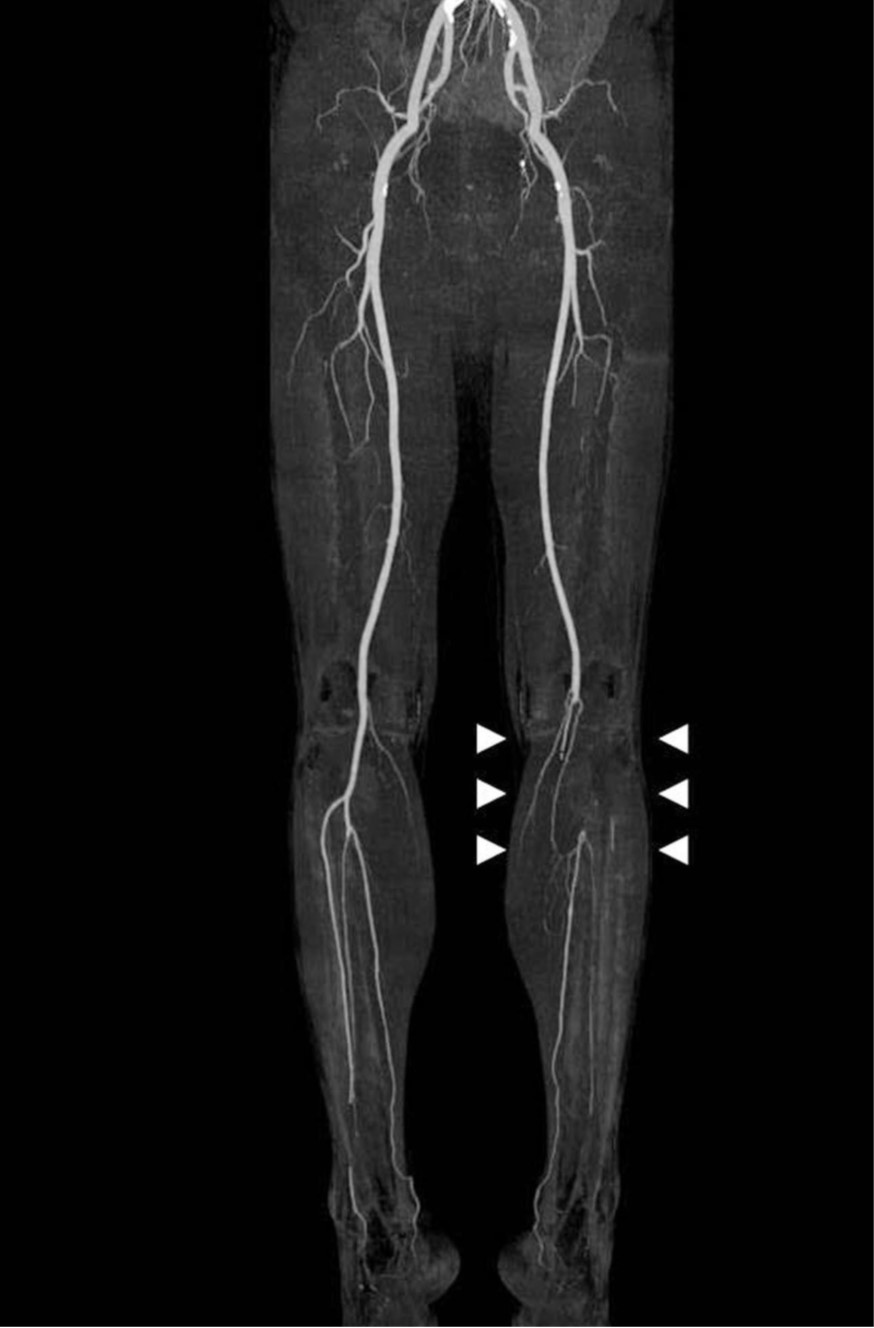

복부 CT에서, 복부대동맥의 신장동맥 분지부에 혈전이 관찰되었음(Fig. 1). CTA에서 좌측 오금동맥에서 후정강동맥의 종아리동맥 분지부까지 긴 분절에 걸쳐 폐쇄가 있었음(Fig. 2).

Fig. 2.

Fig. 2. MIP image from lower extremity CTA shows occlusion of left popliteal artery to anterior tibial artery (white arrows).